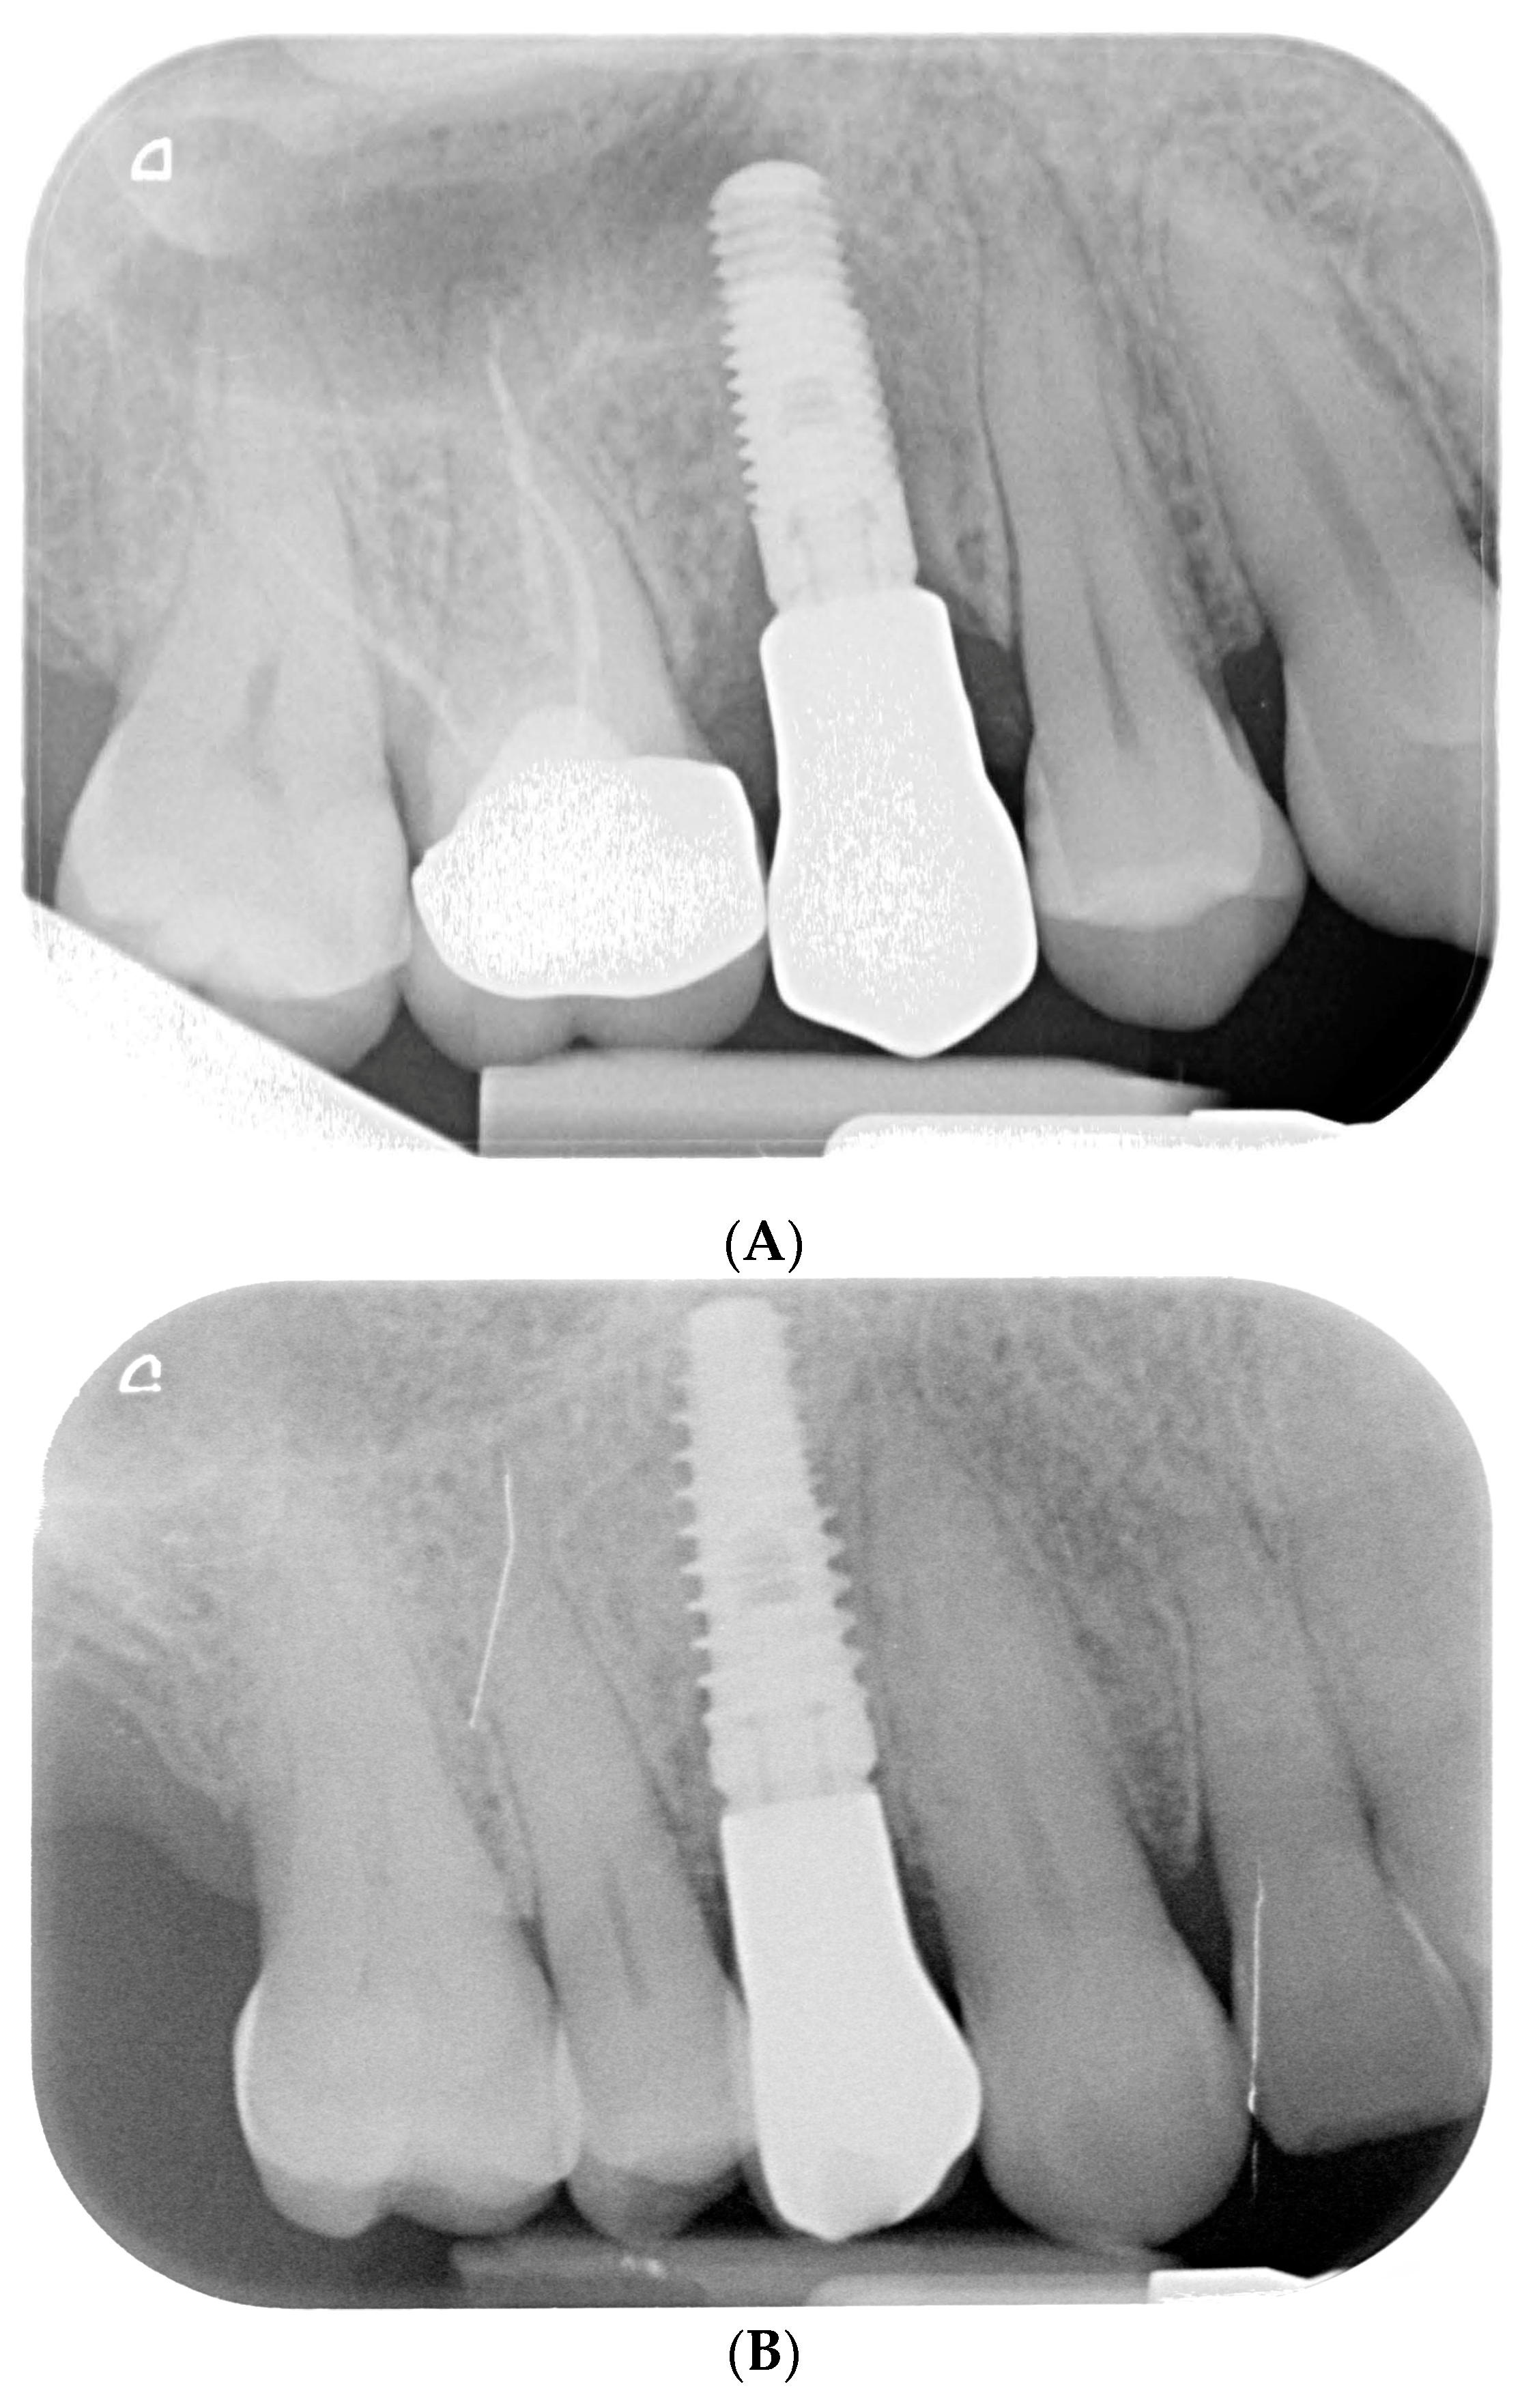

Figure 3.

Endoral RX prior to implant insertion: test group (A) vs. control group (B).

Preoperative examination addressed smile line, inter-arch relationship, and bucco-lingual bone thickness. Periapical radiographs and cone beam computed tomography (CBCT) were obtained to assess root dimensions, bone availability, adjacent structures, and implant planning. Preoperative periapical radiographs were taken using the VistaScan Mini Plus device (Figure 3) (Dürr Dental SE, Bietigheim-Bissingen, Germany).

Endoral RX after final crown delivery. (A) Tooth 1.5; (B) Tooth 1.4.